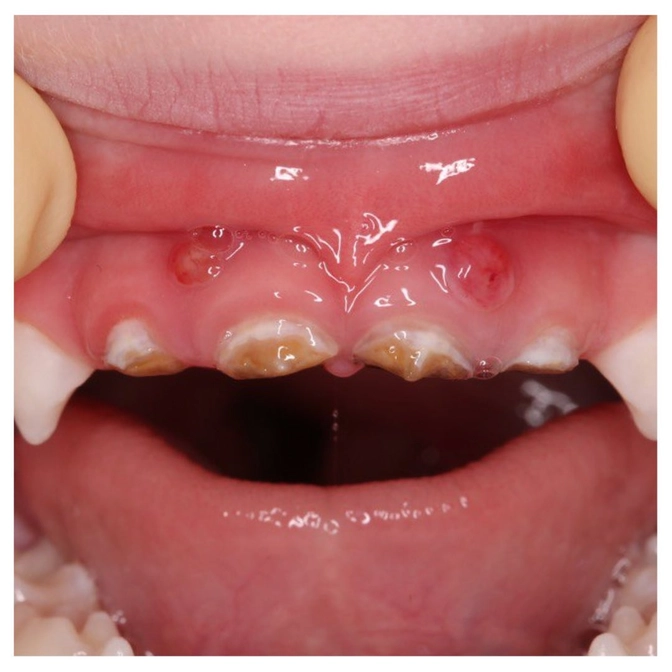

Мама увидела "шарики" на деснах над верхними центральными зубами, обратилась к доктору.

Шарики на дёснах - это свищи.

А свищи появляются не от грязных рук, а от того, что воспаление уже вышло за пределы зубов.

А там и зачатки постоянных зубов недалеко.

Корни молочных при этом рассосались!

А гной от воспаления пошел наружу к краю десны и образовал вот такие "шишки"

Вердикт - центральные верхние резцы УДАЛЯЕМ.